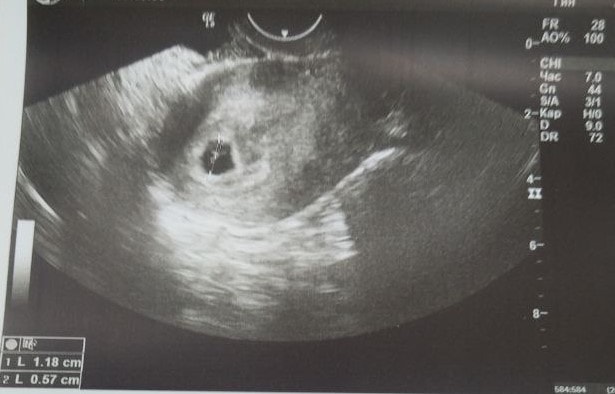

УЗИ 21дпп

Результаты УЗИТеперь я официально считаюсь беременной!))